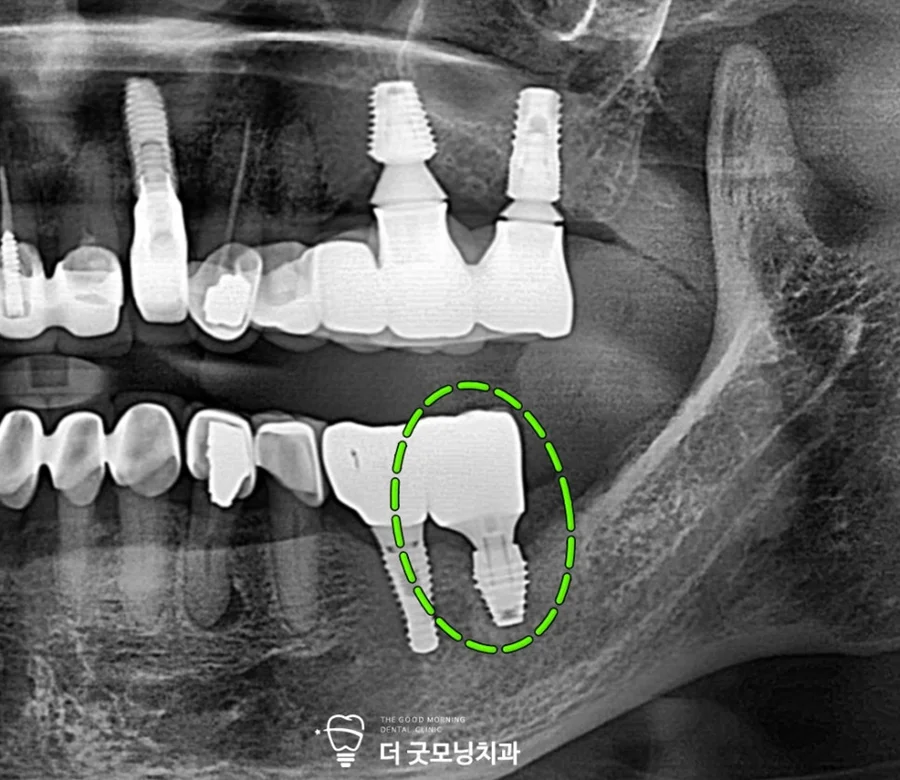

▲ 내원 당시 파노라마 엑스레이 – 37번 픽스처 주위 치조골 흡수 확인

파노라마 엑스레이 촬영 결과, 왼쪽 아래 37번 픽스처 주위의 치조골 라인이 상당히 내려온 것을 확인할 수 있었습니다. 염증이 많이 진행된 상태로, 제거 후 재식립이 필요하다고 판단되었습니다.

또한 양측 하악 2곳의 자연치 치근단에도 염증이 이환되어 있어 추가 치료 계획도 함께 수립하였습니다.